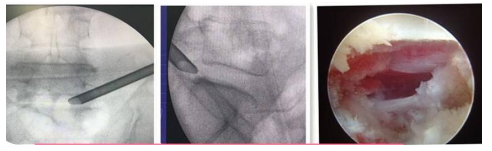

UBE(Unilateral Biportal Endscopic,单侧双通道内镜技术):

UBE(Unilateral Biportal Endscopic,单侧双通道内镜技术)是新兴的一种脊柱外科微创技术,被广泛应用于脊柱退行性疾病(包括腰椎间盘突出症、腰椎滑脱、腰椎管狭窄、颈椎病等)的治疗,收到了较好的临床效果。UBE手术具有视野清晰、创伤小、出血少、效率高、疗效好及恢复快的特点。我院在重庆市较早开展此项技术,多次通过手术直播、学术讲座和实操培训等形式充分展示此项技术。

椎间孔镜技术:

利用椎间孔镜从患者腰椎侧方或者后方进入达到椎间盘突出或者其他病变部位,用专用工具将突出(脱出)的椎间盘组织或病变取出(去除)从而达到治疗椎间盘突出或者椎管狭窄的目的。它的优势在于:局部麻醉、微创、切口小(仅约7mm),出血少,恢复快(第二天即可佩戴硬腰围下地)及疗效好。